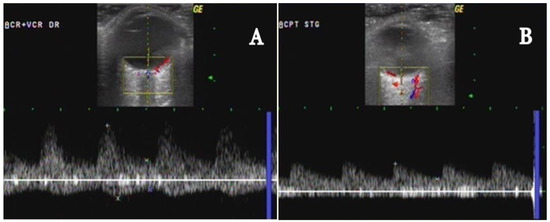

- In the acute phase of unilateral clinical eye involvement, absent (undetectable) signals in the homolateral PCAs (not corresponding to homolateral internal carotid artery occlusive disease) are classified as Doppler US features in acute arteritic AION (consecutive to GCA). In addition, we can identify a high resistance index (RI), with decreased velocities (especially EDV) in all retrobulbar vessels, in both orbits [9,10,11,12,13,14,15,60,61,62] (Table 2) [13].

- GCA acute cases with no evident clinical ocular involvement present a decrease in arterial flow in bilateral orbits, with increased RI, and diminished velocities (especially EDV). The severely diminished flow in the PCA, associated with diminished flow in the CRA and very high flow in the OA (all on the affected side) are the common US features in this type of patient. This US aspect is an essential predictor of an imminent A-AION and needs prompt treatment with high-dose corticosteroids [9,10,11,12,13,14,15,60,61,62] (Figure 7) [11].